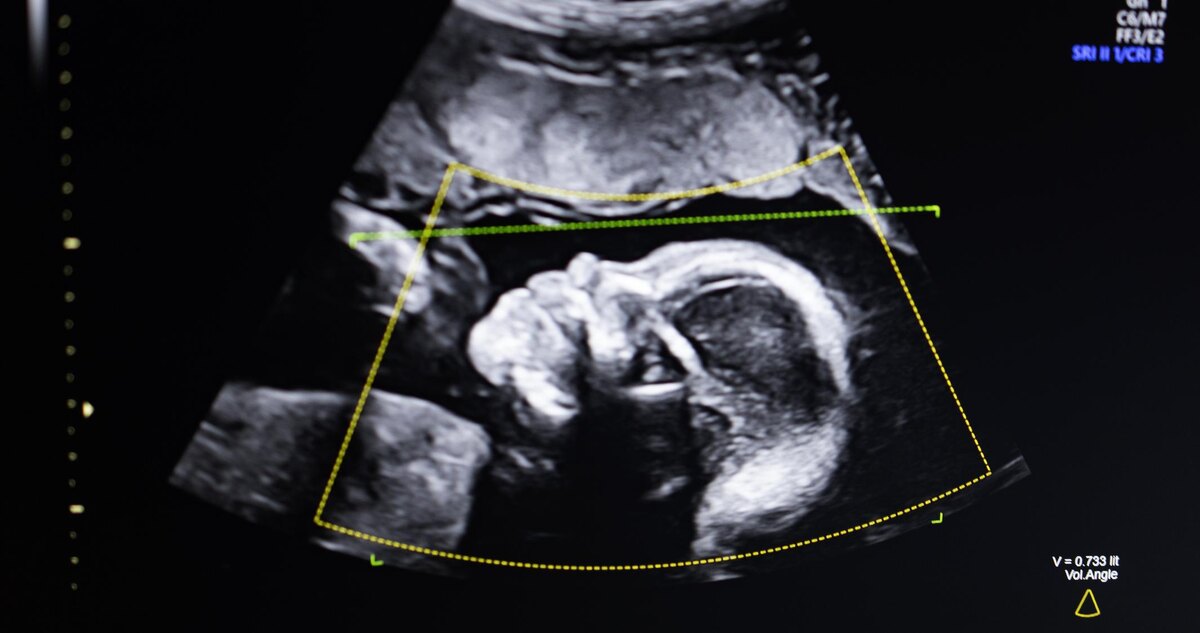

🔥 Biotics AI получила FDA-одобрение для своего AI-софта для выявления аномалий у плода! 🚀

1️⃣ Технология использует компьютерное зрение для оценки качества УЗИ, анализа анатомии и автоматического формирования отчетов

2️⃣ Модель была обучена на 11 000 ультразвуках, что обеспечивает надежность в реальных условиях среди групп с высоким риском

3️⃣ Процесс утверждения прошёл менее 3 лет благодаря тесной интеграции разработки, клинических тестов и регуляторных процедур

Это КОНТРОРЛЕР, способный повысить качество диагностики и снизить смертность матерей — особенно среди чернокожих женщин. КАК это повлияет на медицинский рынок? Гики, что думаете? Следим за обновами!